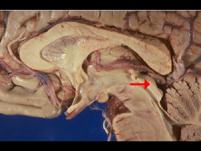

如图箭头所示为大脑哪个部位 ( )A、松果体B、中脑导水管C、后连合D、中央后回E、中脑顶盖

问题 如图箭头所示为大脑哪个部位 ( )

选项 A、松果体 B、中脑导水管 C、后连合 D、中央后回 E、中脑顶盖

答案 E